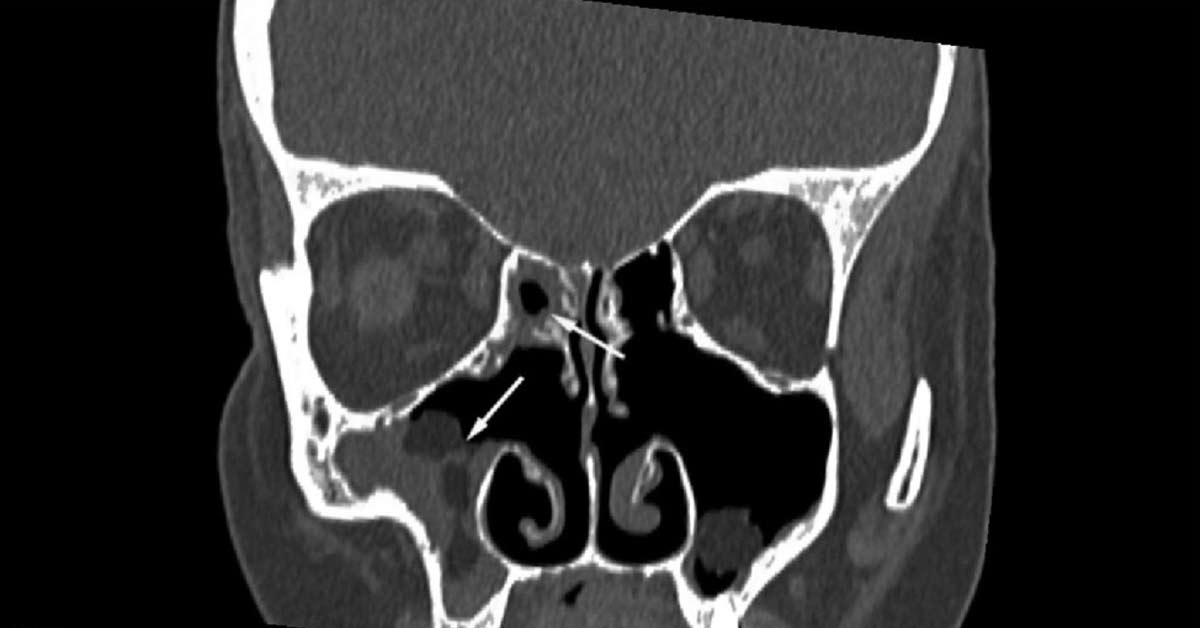

A sinusite esfenoidal crônica afeta os seios da face localizados bem lá no fundo, atrás dos olhos. Por isso, os sintomas podem ser diferentes da sinusite mais comum. A dor de cabeça, por exemplo, costuma ser mais profunda. O médico, geralmente um otorrino, vai te examinar e pode pedir exames como a tomografia computadorizada. É esse raio-x mais detalhado que vai mostrar direitinho a situação e guiar o melhor caminho para você.

| Diagnóstico Preciso | Identificar exatamente o que está acontecendo com sua sinusite. | É o ponto de partida. Sem saber o problema certo, o tratamento fica sem rumo. | Pode ser que você precise de exames como tomografia. Não tenha receio, é para acertar no tratamento. Confie no seu médico. |